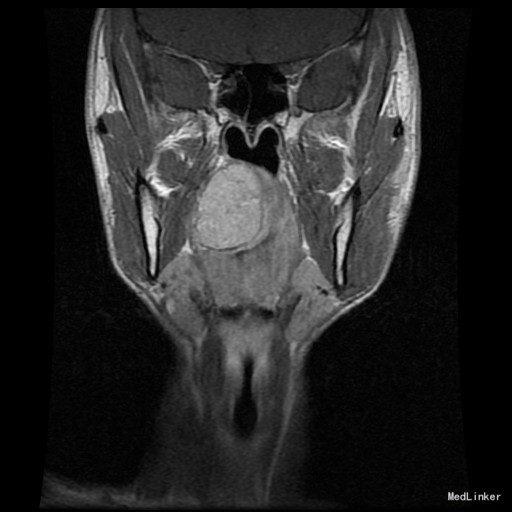

查体:右侧软腭至硬腭处见一肿物,约5*3cm,质硬,固定,边界欠清,表面粘膜光滑。 辅助检查:外院颌面CT提示:右侧软腭实性占位,并累及鼻咽、口咽壁,建议MRI增强检查。

入院诊断:咽旁肿物(右侧软腭肿物性质待查) 治疗:入院后咽部MRI示:软腭右部软组织肿块,性质待定,鼻咽腔及口咽腔明显变窄。,未见手术禁忌,遂于全麻下行“右侧咽旁间隙肿物切除术”,术程顺利,术后未见并发症。病理:多形性腺瘤。